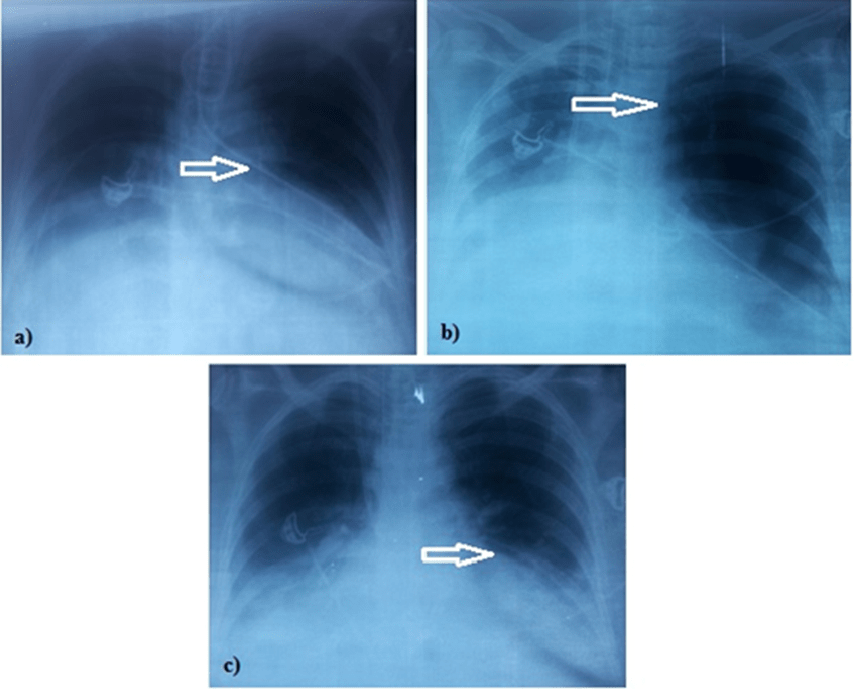

Figure 2. a) Feeding tube incorrectly placed in the left lung. b Feeding Tube In Lung Know the signs and symptoms of tube feeding aspiration: Misplacing a feeding tube risks lung collapse,. Tube feeding is preferred over iv nutrition because it uses the gastrointestinal (gi) tract and is less likely to lead to infection. Acute aspiration of tube feeding can result in a respiratory emergency; Intubation is the insertion of a tube either through the mouth. Feeding Tube In Lung.